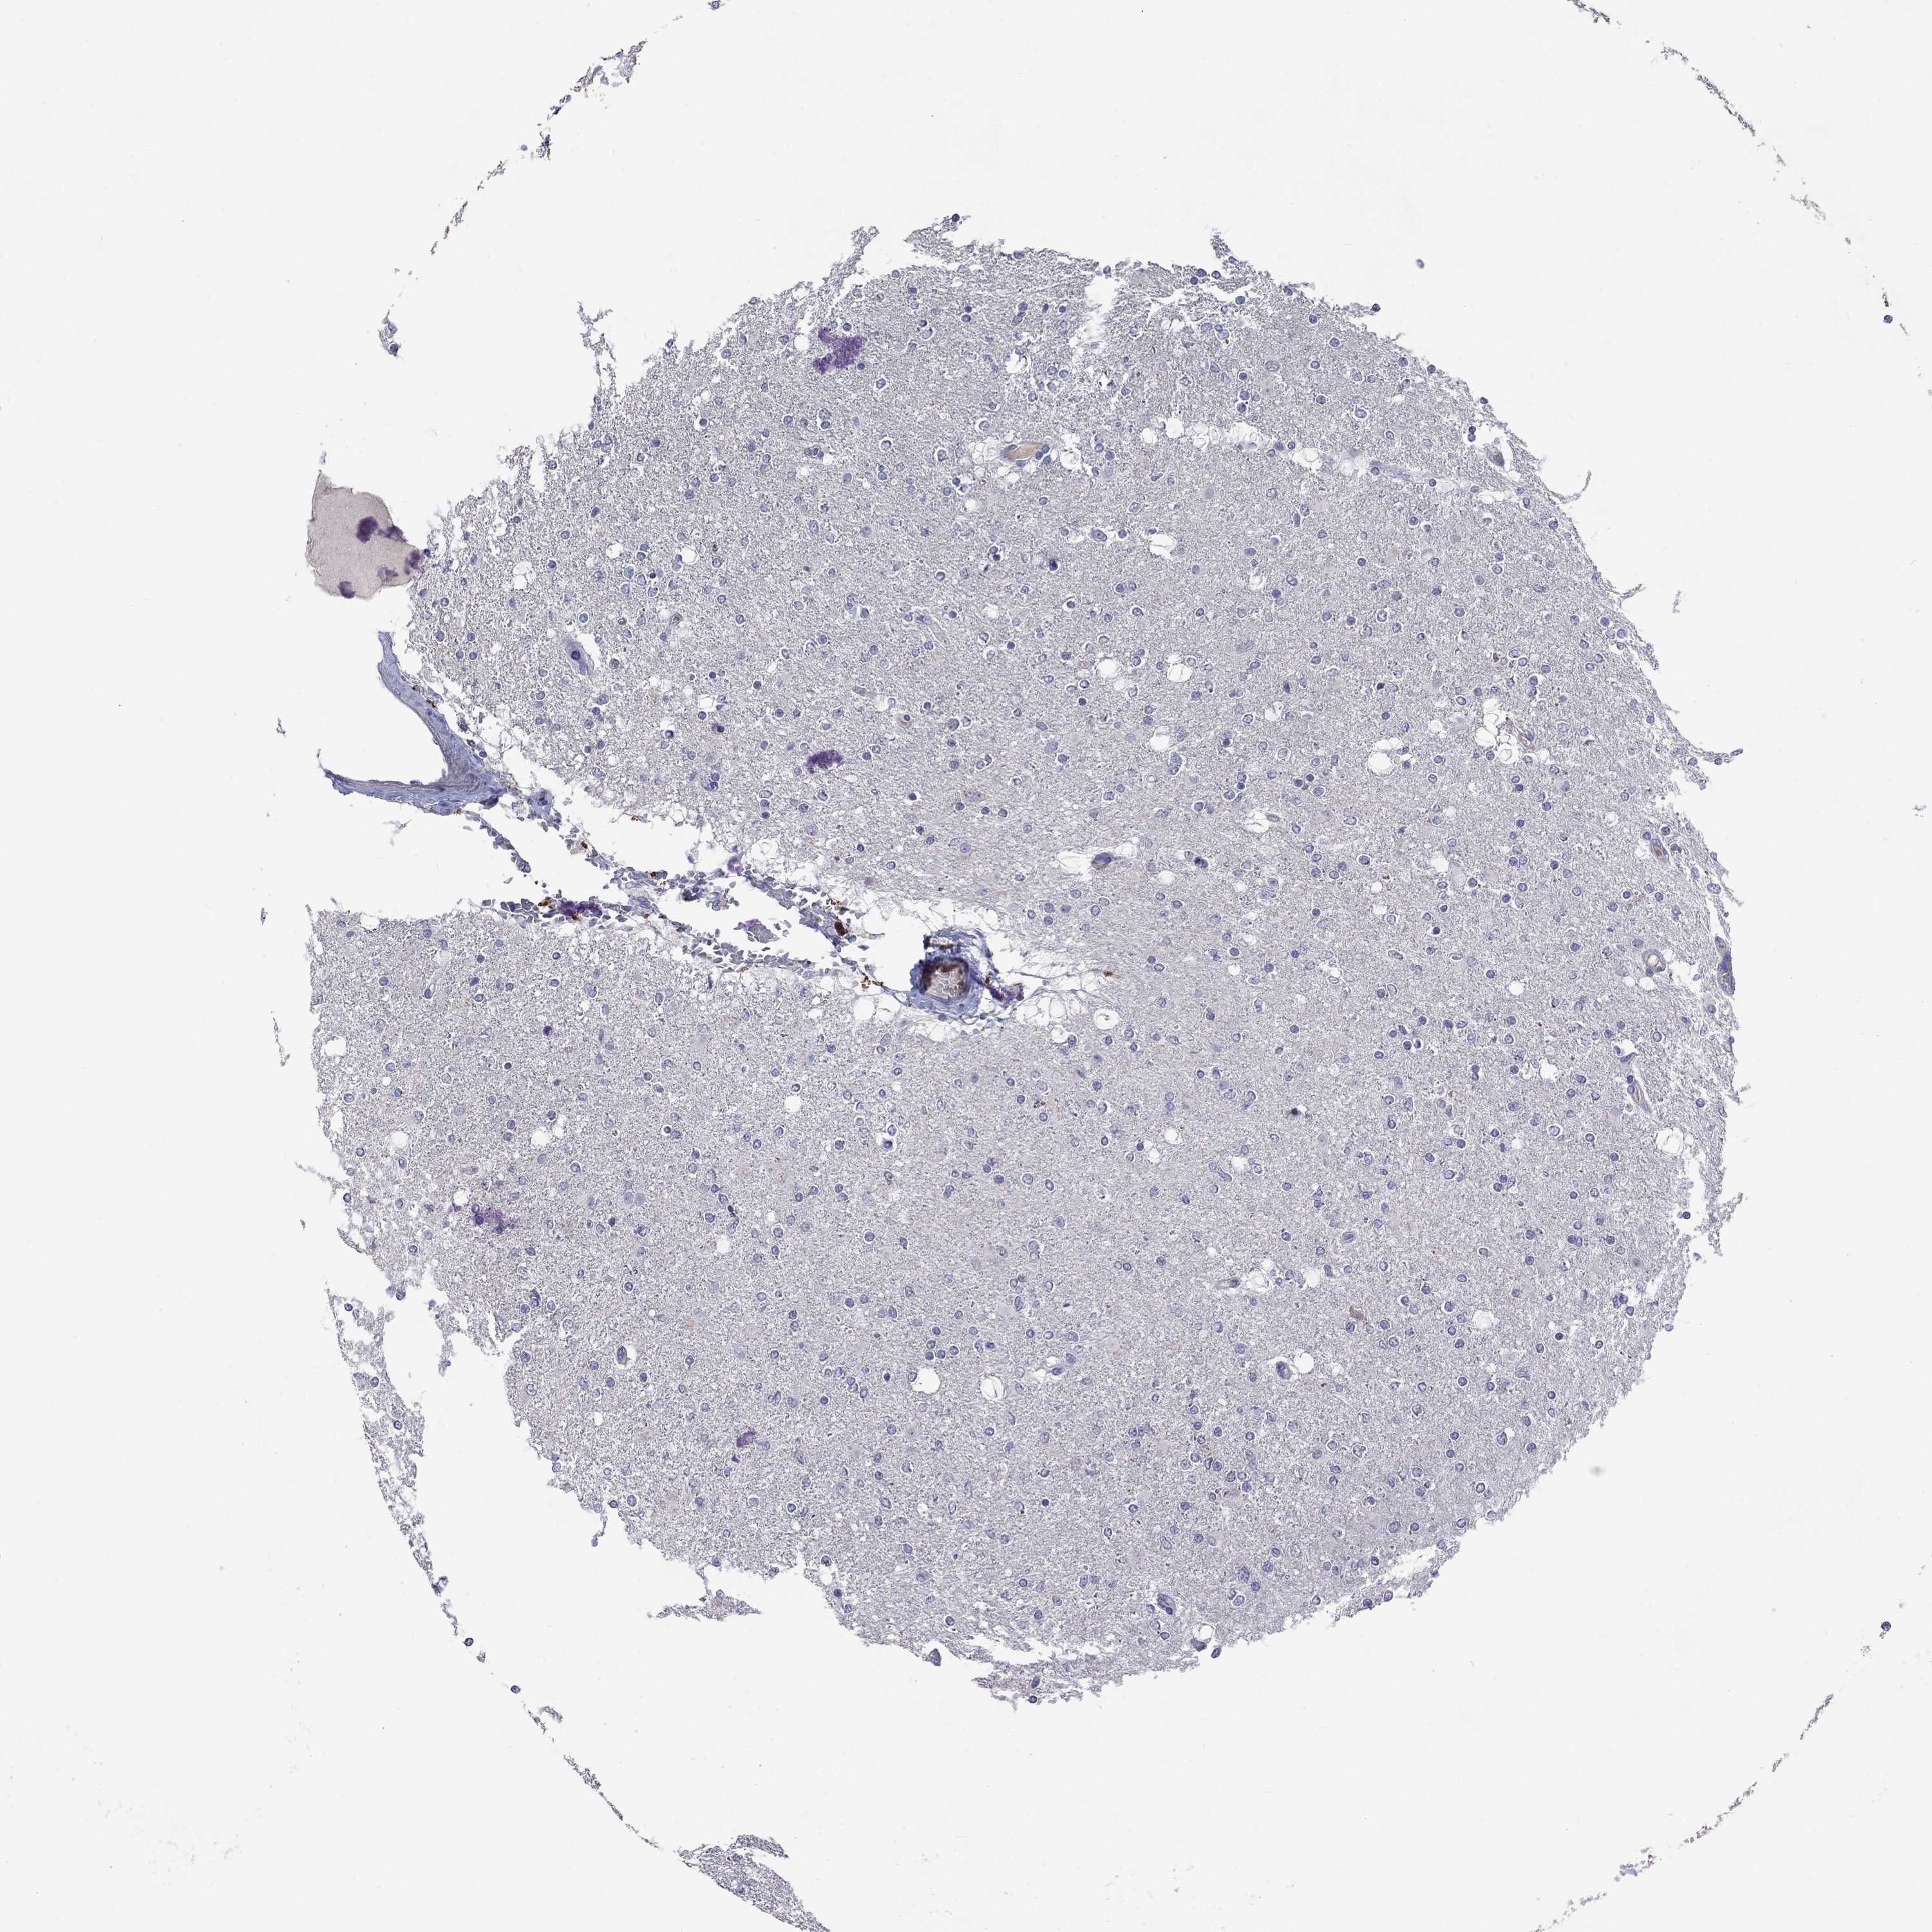

GLIOMA - Protein expressioni

A mouse-over function shows sample information and annotation data. Click on an image to view it in a full screen mode. Samples can be filtered based on level of antibody staining by selecting one or several of the following categories: high, medium, low and not detected. The assay and annotation is described here.

Note that samples used for immunohistochemistry by the Human Protein Atlas do not correspond to samples in the TCGA dataset.

Antibody stainingi

Antibody staining in the annotated cell types in the current human tissue is reported as not detected, low, medium, or high, based on conventional immunohistochemistry profiling in selected tissues. This score is based on the combination of the staining intensity and fraction of stained cells.

Each image is clickable and will lead to virtual microscopy that enables deeper exploration of all samples and also displays staining intensity scores, fraction scores and subcellular localization as well as patient and tissue information for each sample.

Antibody HPA068138

Antibody HPA071902

Glioma, malignant, Low grade

Glioma, malignant, High grade

Glioma, malignant, NOS